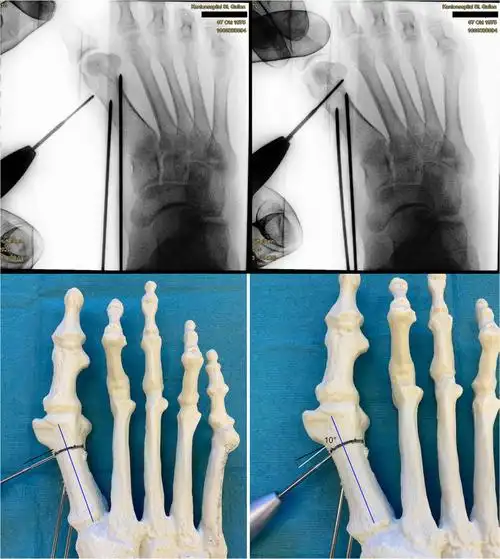

拇外翻角20°-35°,第一跖骨间角 15°,无跖趾关节退变性改变及非手术

拇外翻chevron截骨术